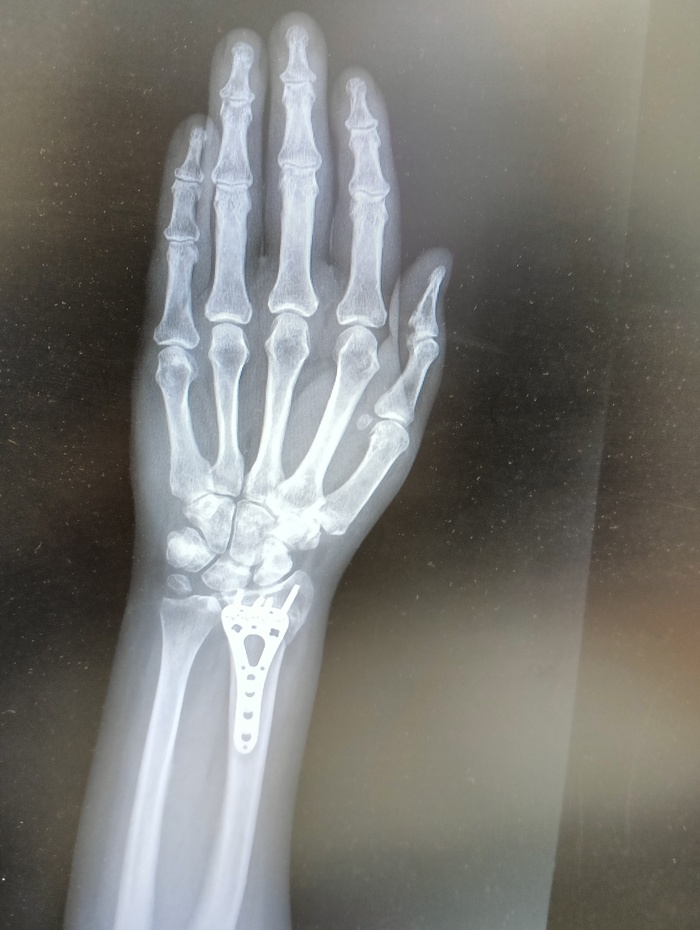

22 июля я неудачно упала и получила оскольчатый перелом дистального метафиза лучевой кости со смещением отломков более чем на 1/2 ширины диафиза. Открытый перелом шиловидного отростка локтевой кости. Была месяц в гипсе, но ничего не срослось. Диастаз костных отломков стал до 4 мм. Локтевая ушла в сторону на 5 мм. На 3 месяц после перелома мне сделали операцию, поставив титановую пластину. Сегодня сделала ренген и получила вот такой результат: Застарелый сомнительно консолидирующийся перелом дистального метафиза правой лучевой кости в условиях накостного МОС. Помимо отрыва шилообразного отростка локтевой кости, видно, имеется разрыв дистального радио-ульнарного сочленения.

Как я понимаю, Шиловидный отросток не прирос и стал болтаться, травмировав ткани внутри... Возможно, что это от реабилитации, я прохожу maps терапию для разработки руки, а может и просто, ведь рукой стараюсь пользоваться.

верхние ффото через 2 месяца после перелома, потом после операции и 2 нижние - сегодня